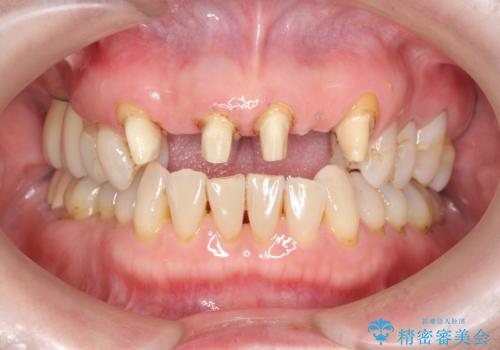

不自然な前歯ブリッジ ジルコニアブリッジによるやり替え

- 20年前に入れたブリッジの見た目の改善を求めて来院されました。

丁寧に現在装着されているブリッジを除去後、精度の高いジルコニアブリッジで審美性の改善を計画します。

- 66万円(仮歯・ジルコニアクラウン×6)費用は治療当時の料金となります

前歯に限らず拡大鏡を用いた精密な形成・シリコンを用いた精度の高い印象を徹底することで治療全体の質を高め、審美性だけでなく長期的な予後を期待することができます。